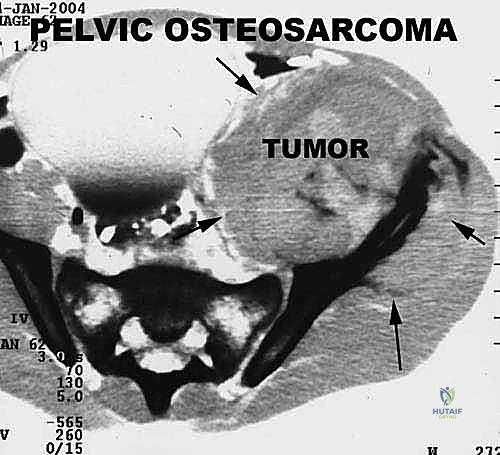

* ساركوما إيوينغ (Ewing Sarcoma): تصيب غالباً العظام الطويلة والحوض.

2. الموقع (Site - T): هل الورم داخل الحيز العظمي (Intracompartmental - T1) أم اخترق القشرة وخرج للحيز الخارجي (Extracompartmental - T2)؟

3. الانتشار (Metastasis - M): هل انتقل الورم لأعضاء أخرى (M0 لا يوجد، M1 يوجد انتشار)؟